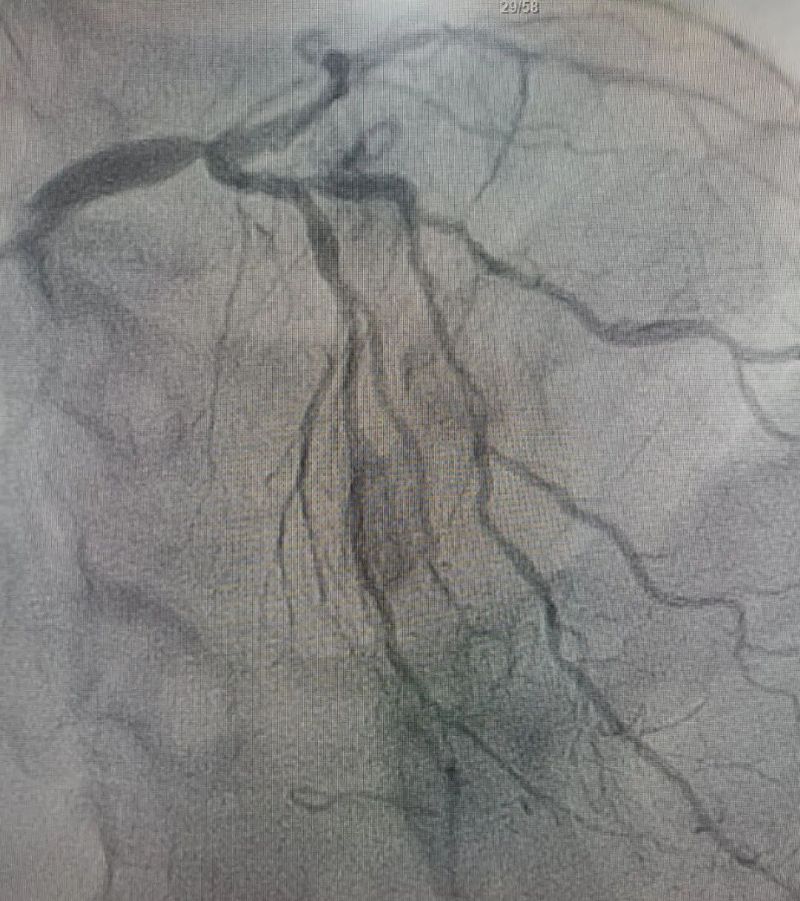

術中造影顯示,左主干至前降支近段重度狹窄——這正是導致心臟缺血、誘發(fā)室顫的“罪魁禍首”。主動脈球囊反搏植入、球囊擴張、支架植入......介入團隊精準操作,一氣呵成。堵塞的血管順利開通,血流重新涌動,這顆一度瀕臨停跳的心臟終于重獲生機。

冠狀動脈造影圖

術前 (左主干至前降支近段重度狹窄)